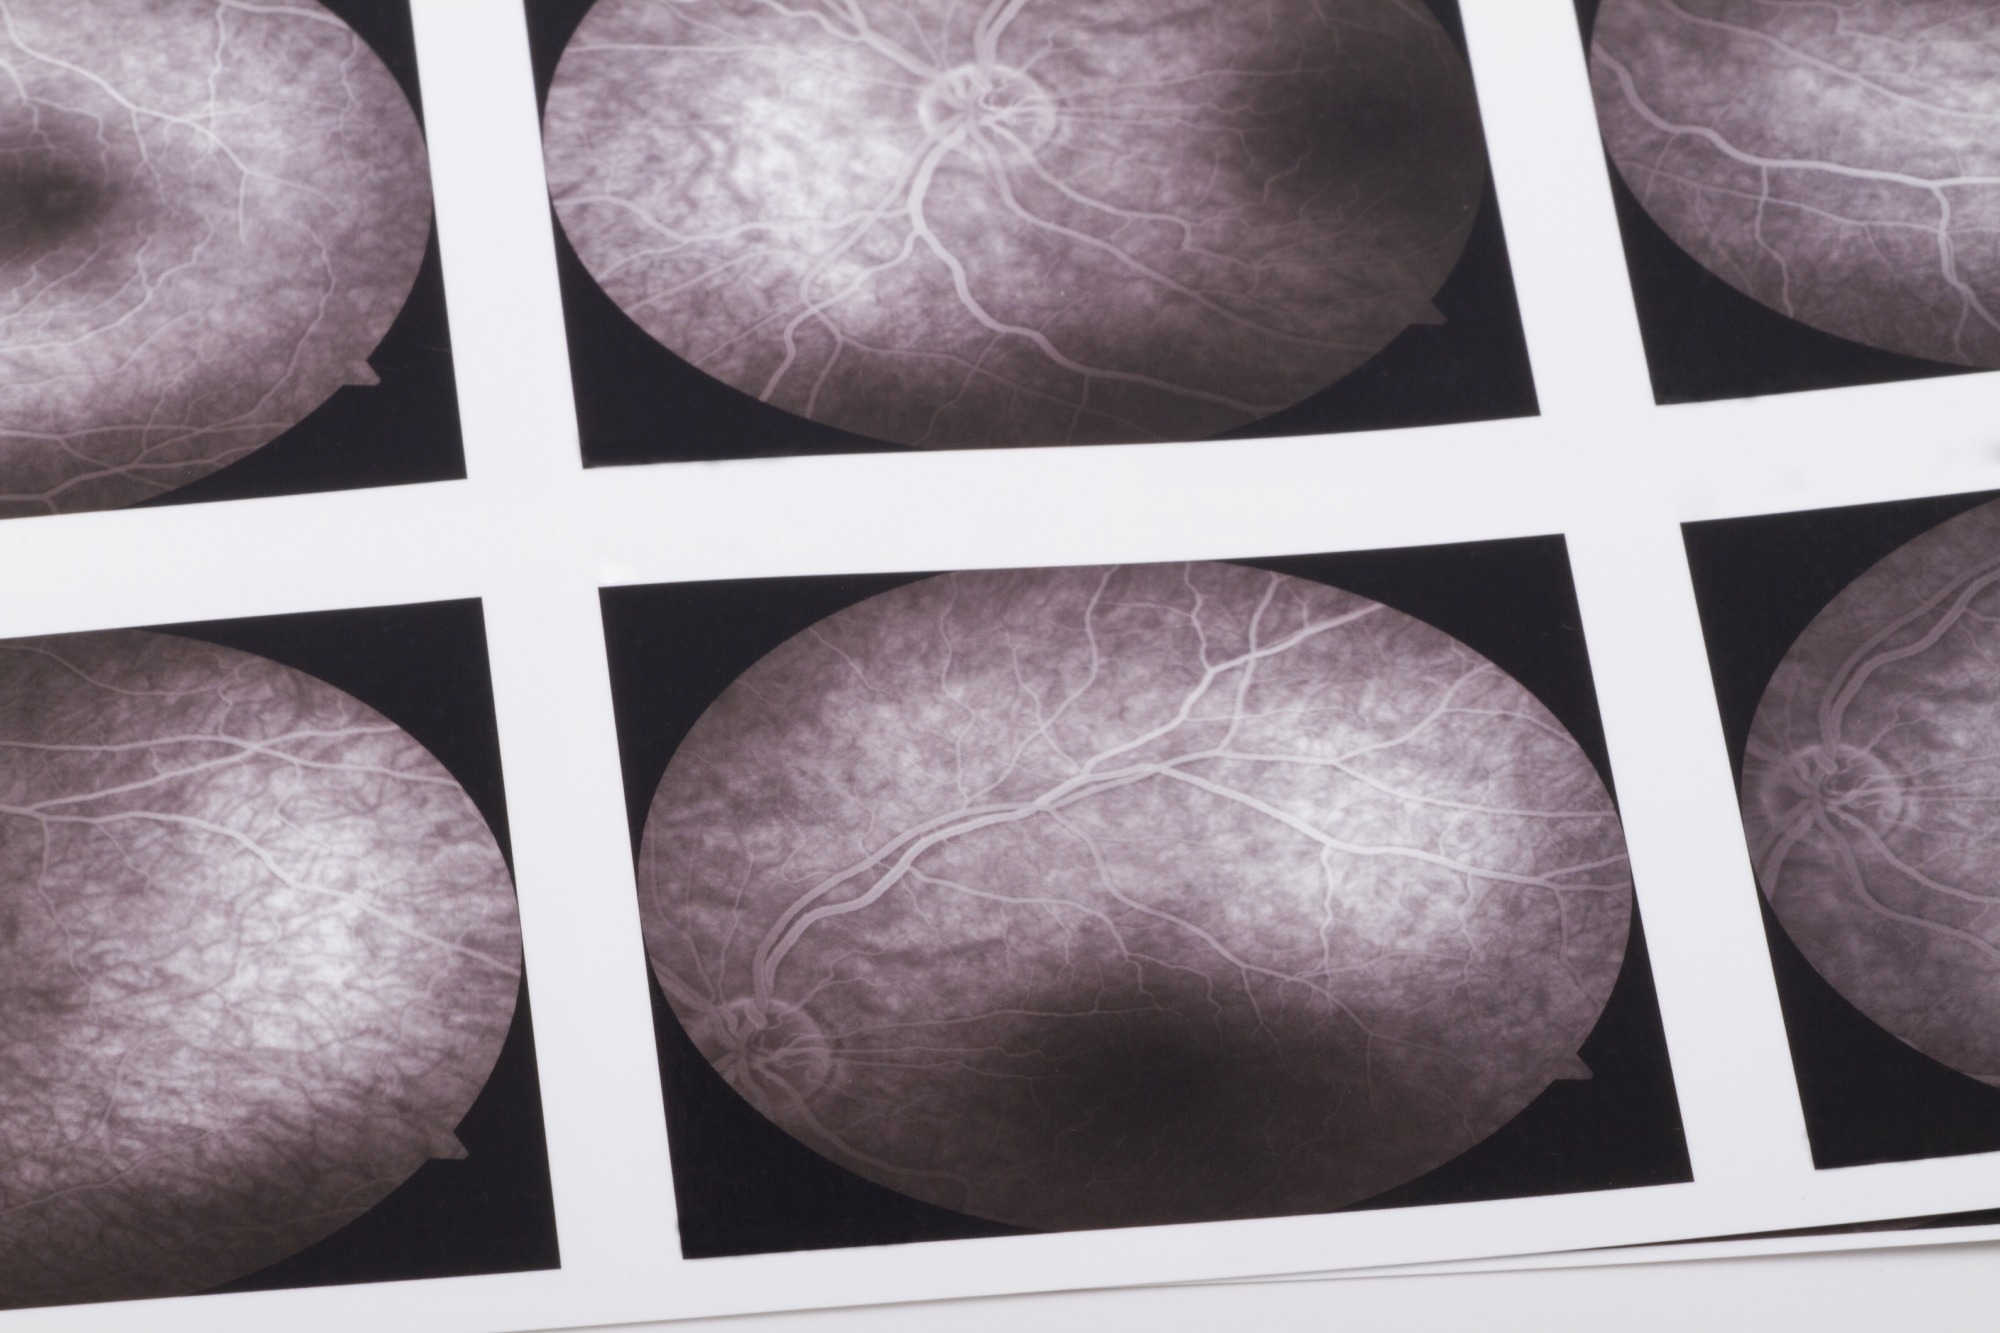

Study: Early detection of dementia through retinal imaging and trustworthy AI. Image Credit: bfk / ShutterstockStudy: Early detection of dementia through retinal imaging and trustworthy AI. Image Credit: bfk / Shutterstock

In a recent study published in the journal NPJ Digital Medicine, researchers have developed a deep learning algorithm capable of analyzing high-resolution images of retinal vasculature to detect Alzheimer's disease (AD) and mild cognitive impairment (MCI) at early stages. This innovative approach could enable clinicians to identify patients with a high risk of dementia, allowing timely pharmacological intervention to slow the progression of the disease and its detrimental effects.

OCTA is a state-of-the-art imaging technique that allows for rapid and noninvasive imaging of the retinal microvasculature, including even the smallest capillaries with a resolution of 5–6μm. This technology provides detailed insights into the microvascular network and the structure of the foveal avascular zone across different retinal layers, as well as the choroid.

In this study, the researchers developed and tested a novel deep-learning model called "Eye-AD." The model was specifically designed to analyze OCTA images and identify patients with early-onset Alzheimer’s disease or mild cognitive impairment. The model processes high-resolution data from various retinal layers, including the superficial vascular complex (SVC), deep vascular complex (DVC), and choriocapillaris (CC), to detect patterns associated with cognitive decline.